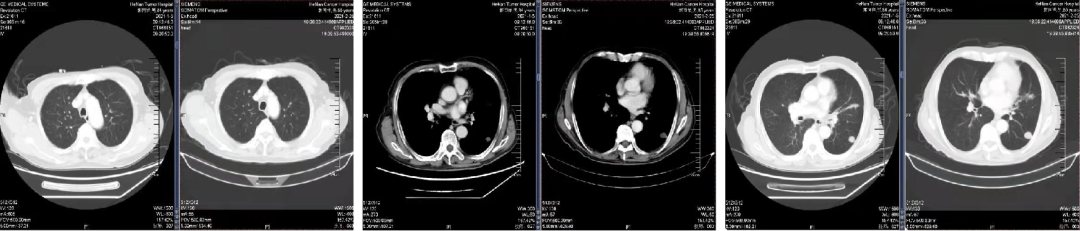

二线治疗

于2021.03.02、2021.03.24 行“卡培他滨+贝伐珠单抗”方案化疗2周期。

三线治疗

于2021.04.14 始行“曲氟尿苷替匹嘧啶片(TAS-102)+贝伐珠单抗”2周方案治疗至今。

04 疗效评估

患者疾病控制良好,耐受情况好。